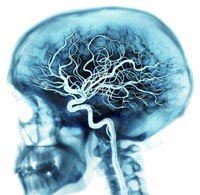

Дуплексное сканирование магистральных артерий головы (ДС МАГ)

Дуплексное сканирование магистральных артерий головы (ДС МАГ) представляет собой не только безопасный, но и высокоинформативный метод ультразвукового исследования (УЗИ), назначаемого при различных заболеваниях сосудов.

По результатам проведенного исследования врач сможет дать оценку состоянию сосудов головного мозга, выявить на ранних стадиях поражения артерий, сужение просвета, стеноз и другие патологии.